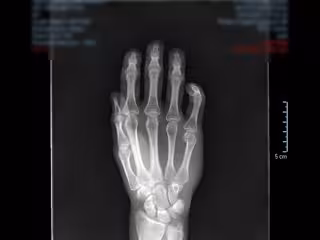

Radiografía de una mano

Radiografía de una mano - QUIRÓNSALUD MARBELLA